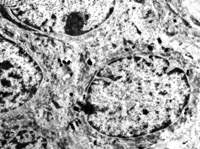

5-2-5 傷后第5天,膠原纖維相互融合,其間的細胞已崩解  TEM×6000